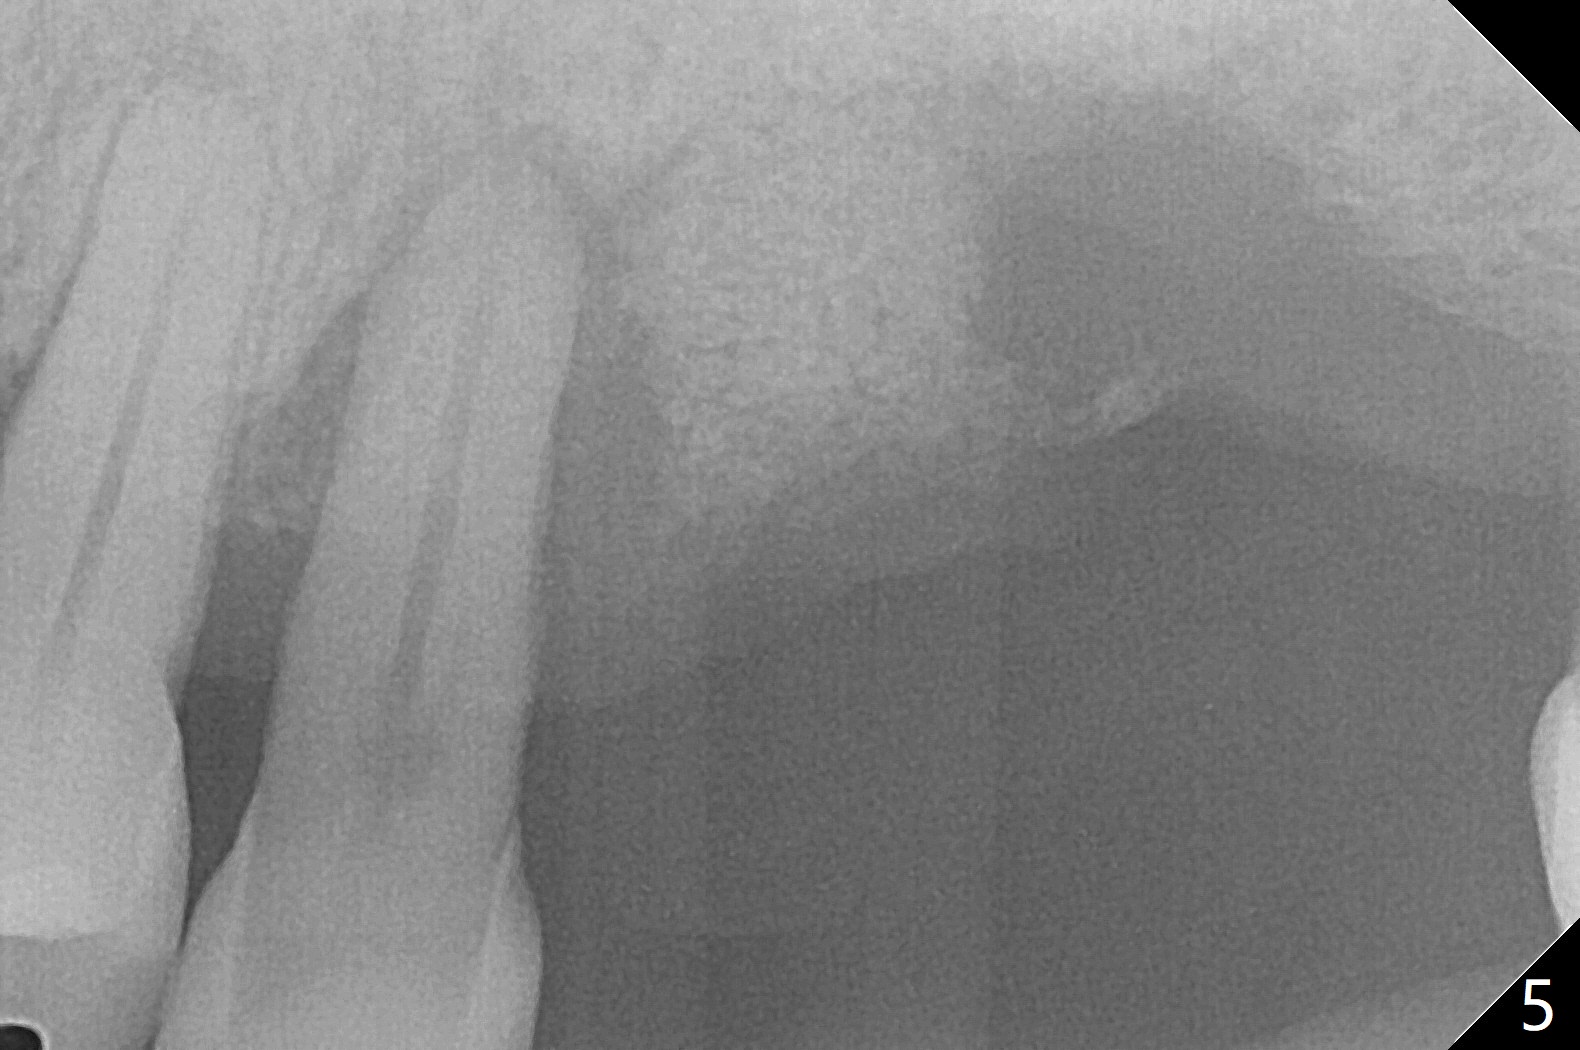

血小板生长因子BB与皮质骨/皮松质骨调合后植入近中颊侧窝(图四G)。今后植牙近远中宽度仿佛不够。13号牙根周阴影(*)是牙髓病(<)还是牙周病?有保留余地吗?图五是另外一张术后即刻根尖片。